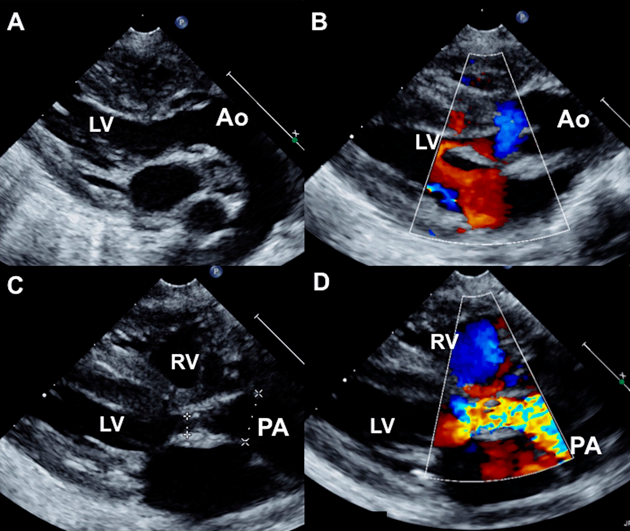

Fig. 4 Echocardiogram of second patient continued (Movie 4)

A modified apical view (A) with color flows (B) show d-malposed aortic origin from the left ventricle and a posterior sweep (C) shows the posterior narrowed pulmonary annulus below the pulmonary artery. The l-malposed aortic relation is seen well on parasternal short axis view. Ao, aorta ; LA, left atrium; LV, left ventricle; PA, pulmonary artery; RA, right atrium.